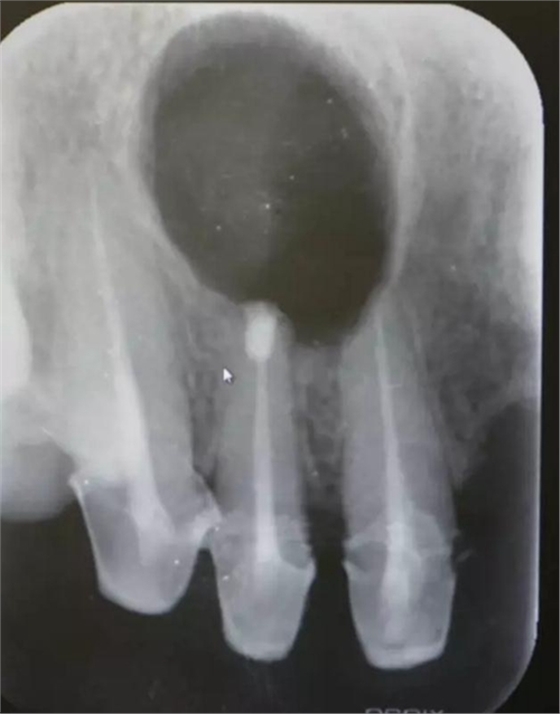

圖1.術(shù)前的根尖片影像檢查:11、12根管治療不完善